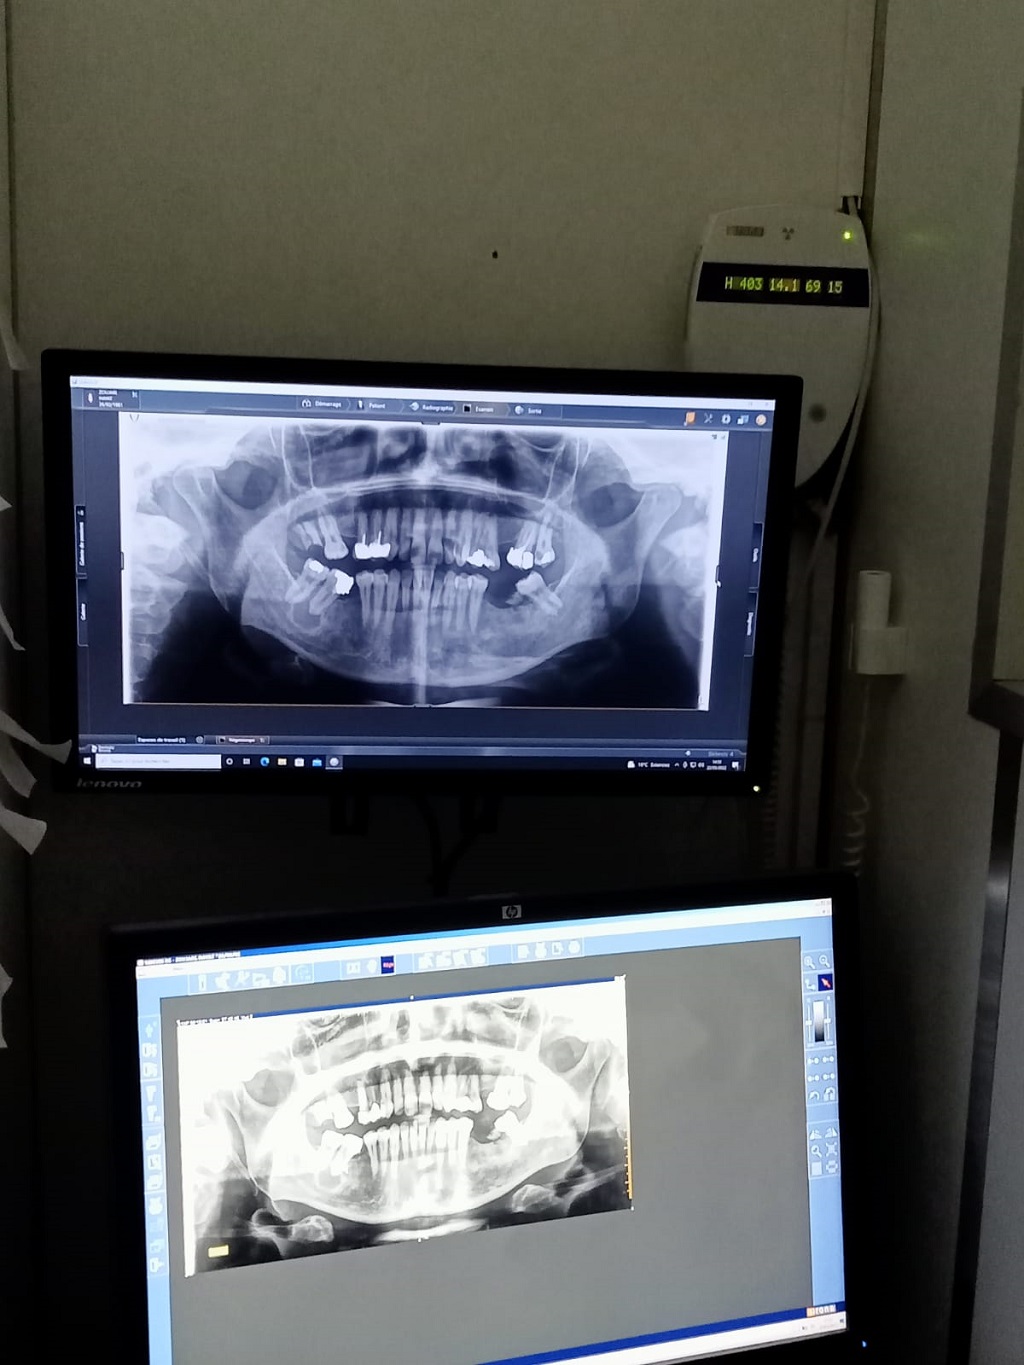

Mais, il est rare de demander une radiographie appelée panoramique des dents dans un but préventif. Que peut apporter cette radiographie spécifique des dents et des mâchoires aussi bien dans le domaine préventif que diagnostique.

Dr Bounhir BOUMEHDI : Elle permet de réaliser un cliché global de la mâchoire afin de connaître l'emplacement exact des dents, repérer diverses anomalies dentaires, déceler les lésions dentaires et des tissus.

On peut observer des caries dentaires, dents de sagesse ou incluses, fractures, kystes, tumeurs, etc.

Par ailleurs, cette radio permet de voir la totalité de la mâchoire, elle est utile pour dévoiler des pathologies comme des infections, des fractures, des dents incluses et des maladies des tissus